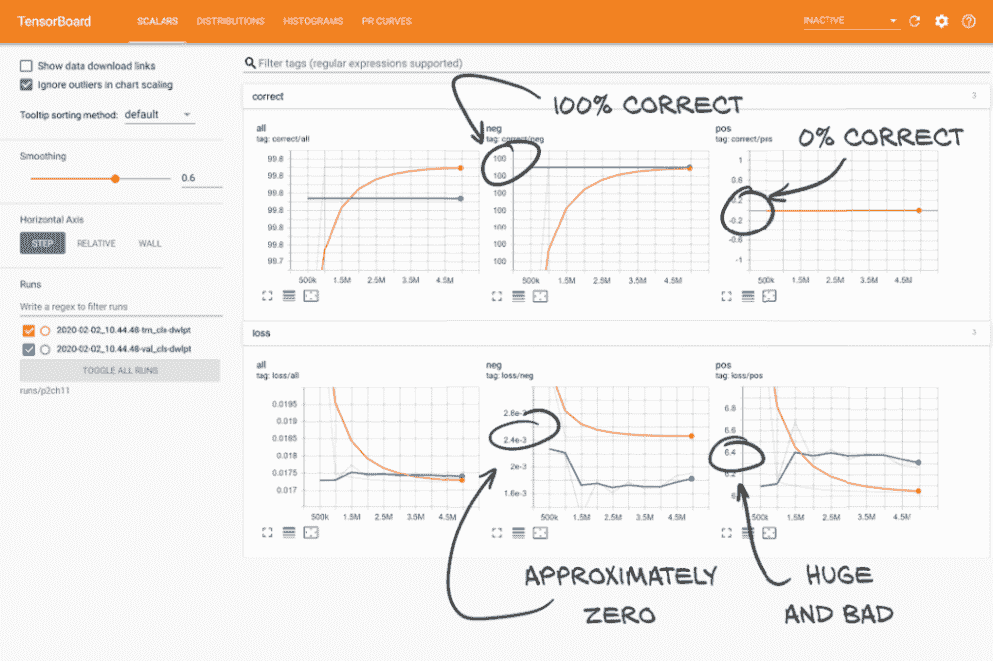

让我们更仔细地(不那么缩减地)看一下第 1 个时代的输出:

E1 LunaTrainingApp

E1 trn 2.4576 loss, 99.7% correct,

E1 trn_neg 0.1936 loss, 99.9% correct (494289 of 494743)

E1 trn_pos 924.34 loss, 0.2% correct (3 of 1215)

...

E1 val 0.0172 loss, 99.8% correct,

E1 val_neg 0.0025 loss, 100.0% correct (494743 of 494743)

E1 val_pos 5.9768 loss, 0.0% correct (0 of 1215)

在验证集上,我们对非结节的分类 100%正确,但实际结节却 100%错误。网络只是将所有东西都分类为非结节!数值 99.7%只意味着大约 0.3%的样本是结节。

经过 10 个时代,情况只是稍微好转:

E10 LunaTrainingApp

E10 trn 0.0024 loss, 99.8% correct

E10 trn_neg 0.0000 loss, 100.0% correct

E10 trn_pos 0.9915 loss, 0.0% correct

E10 val 0.0025 loss, 99.7% correct

E10 val_neg 0.0000 loss, 100.0% correct

E10 val_pos 0.9929 loss, 0.0% correct

分类输出保持不变–没有一个结节(也称为阳性)样本被正确识别。有趣的是,我们开始看到val_pos损失有所减少,然而,val_neg损失并没有相应增加。这意味着网络正在学习。不幸的是,它学习得非常,非常慢。

更糟糕的是,这种特定的失败模式在现实世界中是最危险的!我们希望避免将肿瘤误分类为无害的结构,因为这不会促使患者接受可能需要的评估和最终治疗。了解所有项目的误分类后果很重要,因为这可能会对您设计、训练和评估模型的方式产生很大影响。我们将在下一章中更详细地讨论这个问题。

好的,让我们来谈谈 TensorBoard 的要点:漂亮的图表!屏幕的主要部分应该填满了从收集训练和验证指标中得到的数据,如图 11.12 所示。

图 11.12 主要的 TensorBoard 数据显示区域向我们展示了我们在实际结节上的结果非常糟糕

比起E1 trn_pos 924.34 loss, 0.2% correct (3 of 1215),这样解析和吸收起来要容易得多!虽然我们将把讨论这些图表告诉我们的内容保存到第 11.10 节,现在是一个好时机确保清楚这些数字对应我们的训练程序中的内容。花点时间交叉参考你通过鼠标悬停在线条上得到的数字和训练.py 在同一训练运行期间输出的数字。你应该看到工具提示的值列和训练期间打印的值之间有直接对应关系。一旦你对 TensorBoard 显示的内容感到舒适和自信,让我们继续讨论如何让这些数字首次出现。